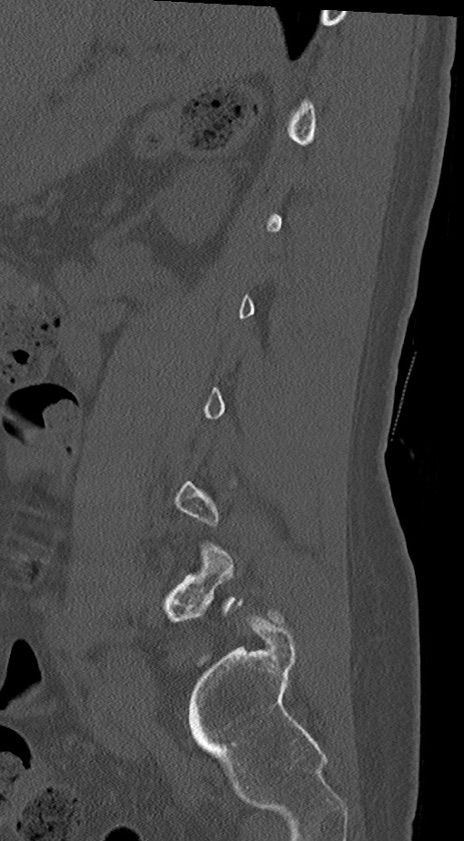

腰椎CT

冠状断像